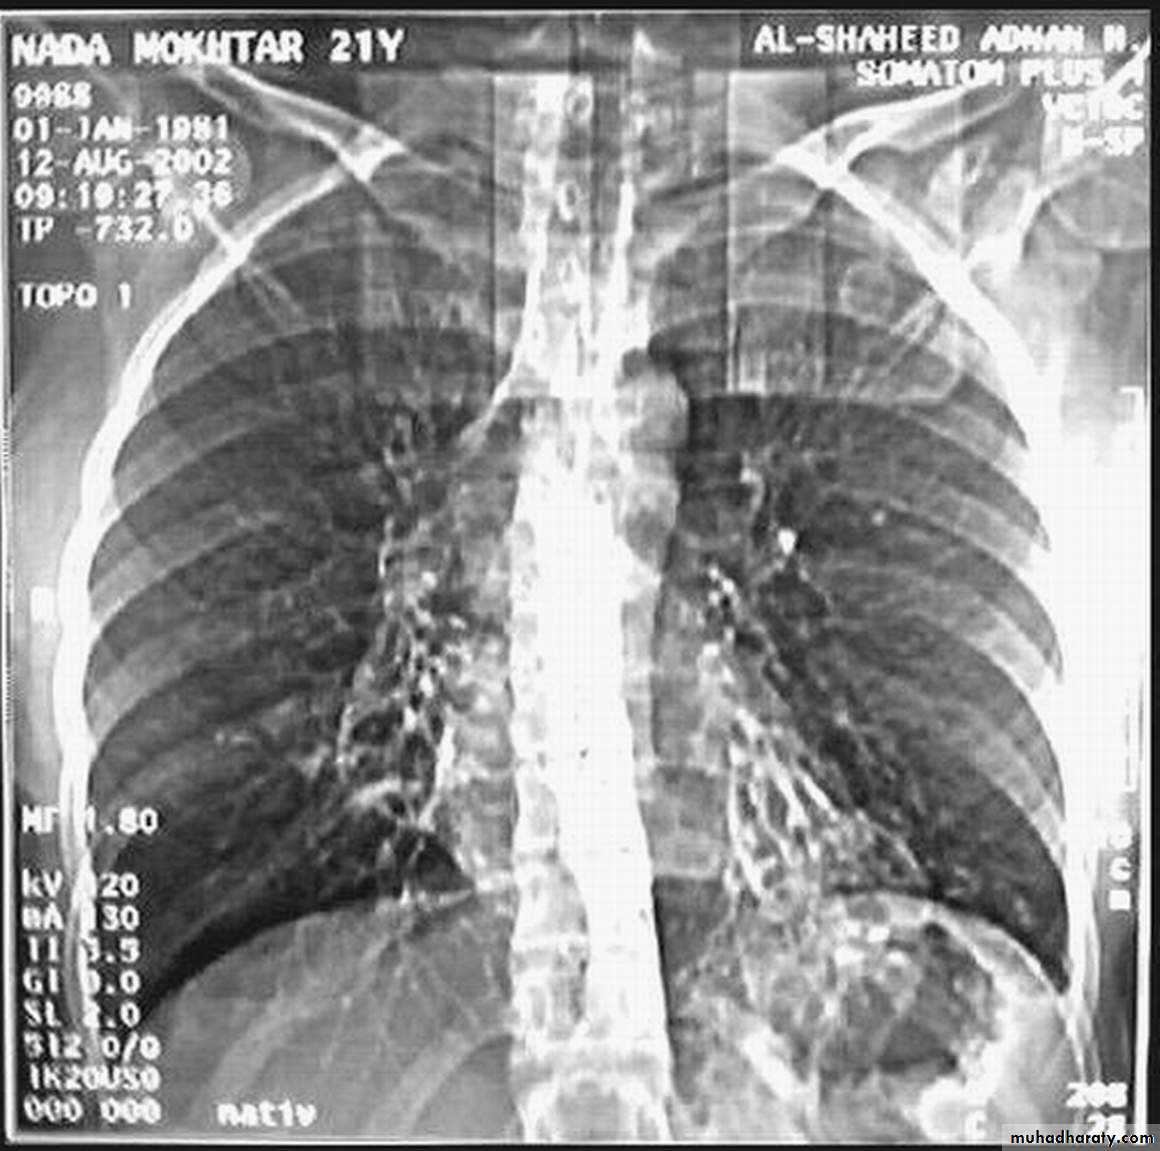

• Radiological Findings

• 1-Smooth homogenous opacity (Intact H.C).• 2-Partial rupture (per vesicular pneumocyst).

• 3-Complete rupture (Water –lilly sign) .

• 4-Formation of lung abscess(Air –fluid level) .

• 5-Completely coughed out cyst(empty cavity )

• 6-Rupture into the pleura (hydropneumothorax)